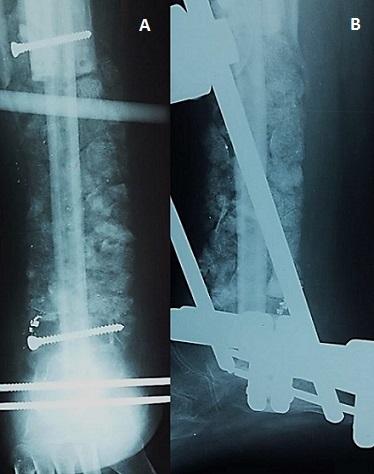

Chondroblastic osteosarcoma, representing about 25% of osteosarcoma, is a fatal primary malignancy of the skeleton if not diagnosed and treated appropriately. It most commonly occurs in the long bones of the extremities near the metaphyseal growth plates. In this report, we describe the occurrence of chondroblastic osteosarcoma involving the left distal tibia in a 14-year-old male. The diagnosis was confirmed by the histological examination of a surgical biopsy. The patient was treated by both surgery and neoadjuvant chemotherapy. No recurrence was noted at 3 years of follow-up. To our knowledge, only two cases describing chondroblastic osteosarcoma of the distal tibia had been reported through English medical literature. Therefore, the aim of our article is to make the clinician aware of this rare clinical presentation and also to provide a comprehensive review of the literature related to this uncommon malignant tumour.

软骨母细胞性骨肉瘤约占骨肉瘤的25%,如果未得到恰当的诊断和治疗,它是一种致命的原发性骨骼恶性肿瘤。它最常发生于四肢长骨靠近干骺端生长板的部位。在本报告中,我们描述了一名14岁男性发生于左胫骨远端的软骨母细胞性骨肉瘤。通过手术活检的组织学检查确诊。患者接受了手术和新辅助化疗。随访3年未发现复发。据我们所知,通过英文医学文献仅报道过2例关于胫骨远端软骨母细胞性骨肉瘤的病例。因此,我们本文的目的是让临床医生了解这种罕见的临床表现,并对与这种罕见恶性肿瘤相关的文献进行全面综述。